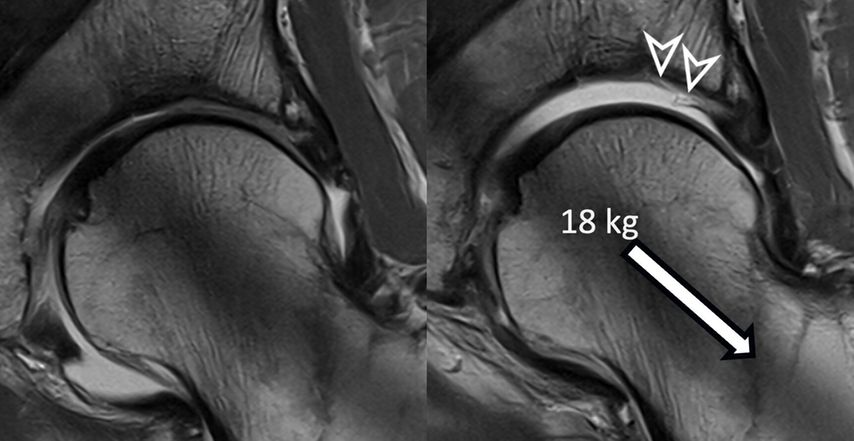

Fig. 1: Traction MR arthrography allows for better visualization of the opposing acetabular and

The hip is a ball-and-socket joint with the labrum dividing it into peripheral and central compartments. In standard MR arthrography, a contrast agent expands the hip capsule and flows into the central joint cavity through the acetabular notch. However, most of the contrast does not spread centrally due to the opposing femoral and acetabular cartilage layers, which typically prevent its accumulation unless there is significant cartilage damage. Therefore, visualizing acetabular cartilage delamination which represents a typical and frequent finding in patients with cam-type FAI is challenging with direct MR arthrography.4

To improve visualization of the central joint cavity during MR arthrography, axial leg traction can be applied, similar to the joint distraction needed during hip arthroscopy (Fig. 1). Traction MR arthrography of the hip has shown high accuracy in detecting chondrolabral lesions, ligamentum teres injuries, and intra-articular loose bodies and has demonstrated its value in predicting failure of FAI surgery.5–8 It is particularly helpful for better visualizing the extent of cartilage damage in older patients with mild radiographic joint degeneration and thus aid in surgical decision making. Traction MR arthrography can also detect unstable labral tears in patients with hip dysplasia and may aid in planning treatment for femoral head necrosis in young patients with early collapse and preserved joint space.4